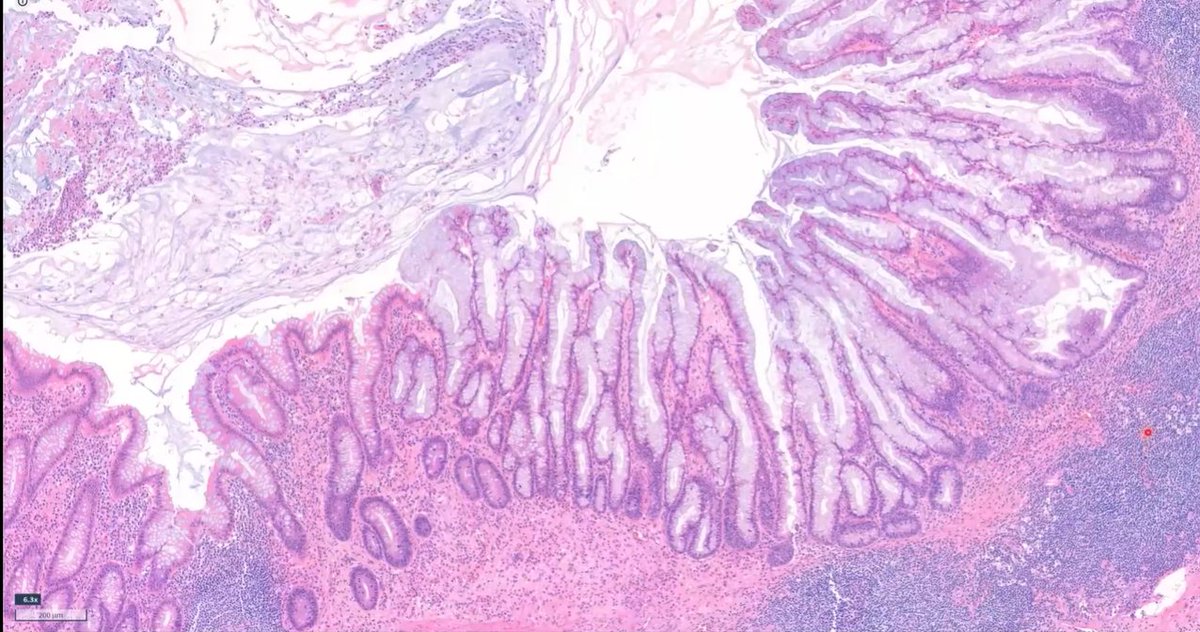

Appendiceal Serrated Lesions They resemble colonic SSLs but are biologically distinct: - Frequent KRAS mutations (unlike colonic SSLs that favor BRAF mutations) - Associated carcinomas are almost exclusively MMR-proficient Dr. Drage - 46th Annual Current Concepts in Surgical